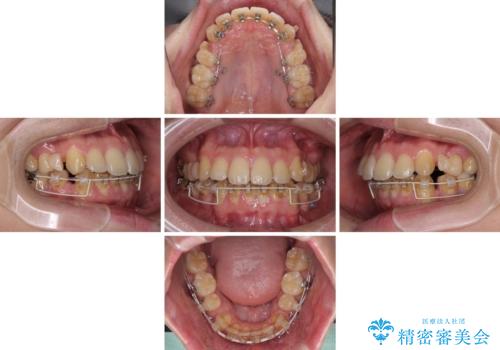

出っ歯と八重歯 目立たない裏側装置でスッキリとした口元に

- 20代男性

- 矯正装置

- ハーフリンガル

- 上顎の前突感による口の閉じにくさと八重歯を気にして来院された患者様です。

目立たない装置を希望されたので、上顎が裏側装置のハーフリンガルを選択し、上下左右の小臼歯(計4歯)を抜歯して矯正治療を行うこととしました。

下顎骨が左側に大きく変位しているため、上下の正中位置は極力一致するところをゴールとしました。

上下顎で左右差の大きい抜歯矯正を裏側装置で行ったため、非常に時間がかかりましたが、正中位置も良い位置に改善され、気になっていた突出感も解消されました。